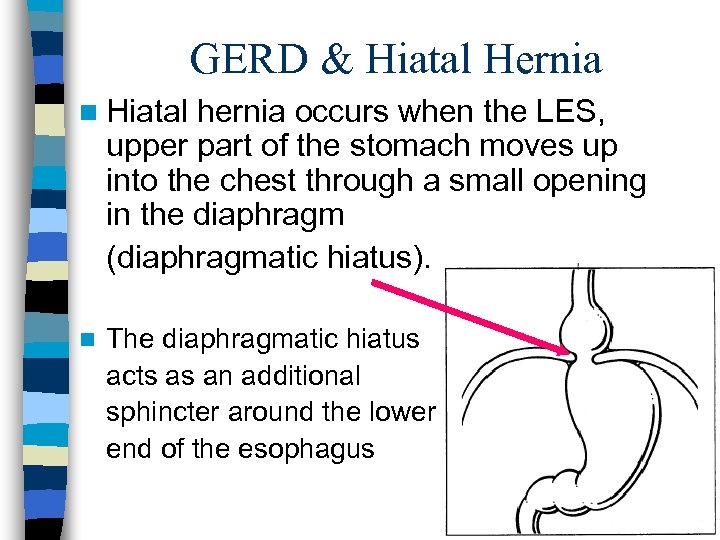

GERD & Hiatal Hernia n Hiatal hernia occurs when the LES, upper part of the stomach moves up into the chest through a small opening in the diaphragm (diaphragmatic hiatus). n The diaphragmatic hiatus acts as an additional sphincter around the lower end of the esophagus